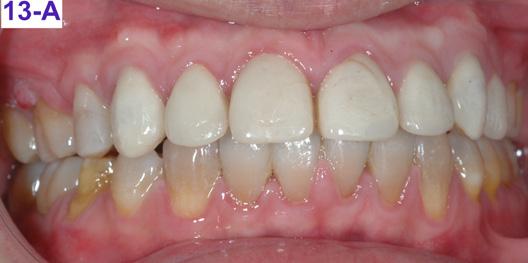

Please view the post-treatment images at the time of insertion of the retainers (Figure 13 – A, B, C. D, E, F, G, H, I, J, K, L).

FIG. 13A: Post-treatment, fontal view